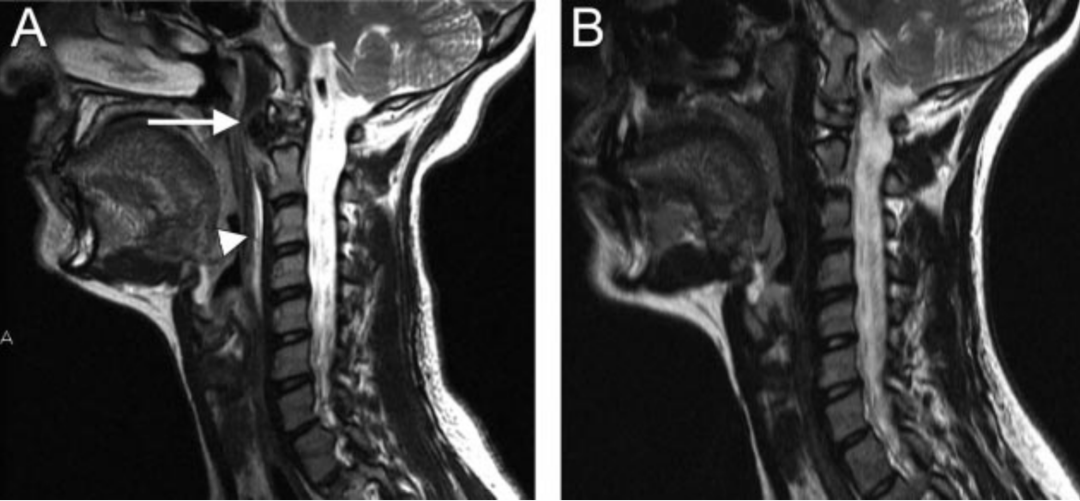

图:C2-3儿童颈椎间盘钙化合并后纵韧带骨化虽然本病可以发生在从新生儿到青春期, 但其发病高峰为6~10岁,男性多于女性,发病部位以颈椎间盘最为多见,胸椎次之,腰椎最少,颈椎中以C6-7和C3-4节段最为常见。一般为单一节段的椎间盘钙化,少数病例也可有两个部位的椎间盘钙化,部分病例可伴有后纵韧带骨化。另外,部分病例可出现神经刺激症状,且在影像检查中不仅可以看到椎间盘异常征象,还可显示肿块侵入椎管,甚至压迫脊髓,特别是合并后纵韧带骨化的病例,椎管侵占率往往大于50%。

图:患者8岁,女孩,因严重颈部疼痛、活动受限伴左上肢无力、麻木不适2天就诊。既往有锁骨骨折、额部软组织挫伤病史。查体:颈椎活动受限,左上肢肌力正常,但感觉减退。白细胞、血沉、CRP升高。颈椎侧位片和CT平扫提示C6-7椎间盘钙化(粗箭头)和后纵韧带骨化(细箭头),颈椎MRI提示C6-7水平脊髓明显受压。给予颈椎制动、枕颌带2.5kg颈椎牵引2周。随后,颈托固定1个月。2年后随访复查颈椎CT如下图,同时上述症状完全缓解。

图:2年后复查CT示C6-7钙化的椎间盘和后纵韧带骨化都消失了

图:8岁女孩,因颈腰痛伴左上肢放射痛2月余就诊,颈椎侧位片、CT和MRI表现与上述病例类似。

图:给予保守对症治疗(具体不详)1月后症状消失。6个月时随访可见钙化的椎间盘和后纵韧带都消失了。